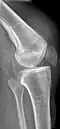

An x-ray demonstrating quadriceps tendon rupture. Note the abnormal angle of the patella and soft-tissue swelling marked by the arrow.